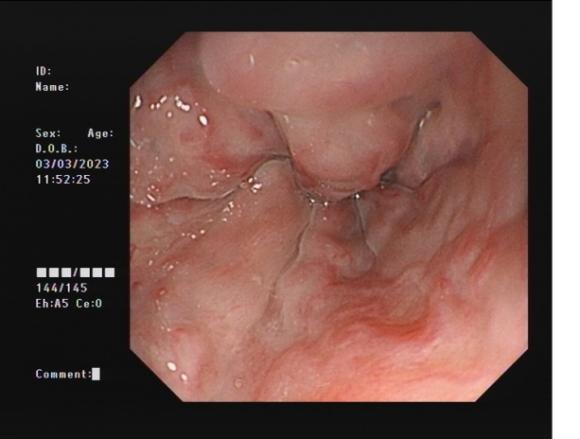

0d0b80a96701483cbcbf8b67351feac3.Jpeg8f7177645651428ca3a0f3c87dfd559d.Jpeg

直腸側向發育性腫瘤      內鏡下黏膜下剝離術后創面

內鏡下黏膜剝離術(ESD):治療巨大平坦息肉,早期癌及癌前病變,黏膜下腫瘤等。